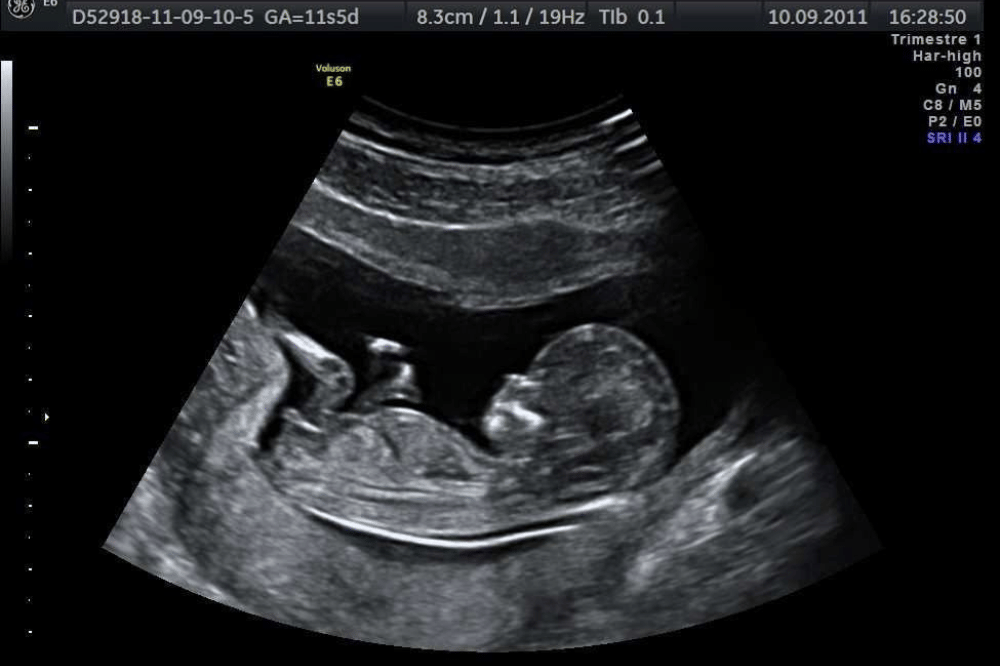

Trimester pertama (sekitar 11–13 minggu)

Secara teknis, penentuan jenis kelamin bayi melalui USG sudah bisa dilakukan sejak minggu ke-11, menggunakan metode seperti genital tubercle angle atau nub theory. Namun, akurasinya masih terbatas. Sebuah penelitian yang dipublikasikan pada PubMed, menunjukkan bahwa tingkat keberhasilan identifikasi saat ada indikasi sudah cukup baik untuk kehamilan 12–13 minggu, yakni mencapai sekitar 94,8% lalu meningkat menjadi hampir 100% pada minggu ke-13.